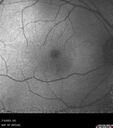

70 year old female with vision loss in the left eye 4 months after cataract surgery.

VA 20/32 OD, 20/80 OS

Images show CME but also a choroidal macrovessel in the left eye.